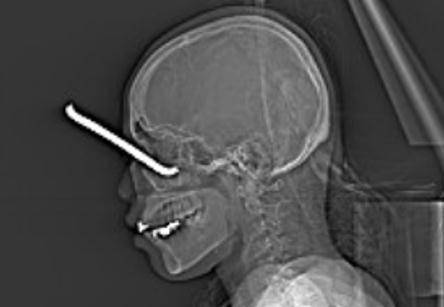

近日 , 一名29岁的姑娘被钢筋扎入左眼 , 眼鼻鲜血直流 , 情况非常紧急 , 由于附近医院无法处理 , 当天下午 , 患者被紧急转诊至广西壮族自治区人民医院救治 。

医院眼科张九明副主任医师经过检查 , 发现钢筋扎得特别深 , 贯穿了整个左眼眶扎入上颌窦及鼻道中 , 严重破坏了周围的重要神经和血管 , 眼外肌及视神经已显示不清 , 患者的视力仅剩光感 , 必须紧急拔出钢筋抢救眼球 。

术前CT显示

钢筋贯穿左眼眶